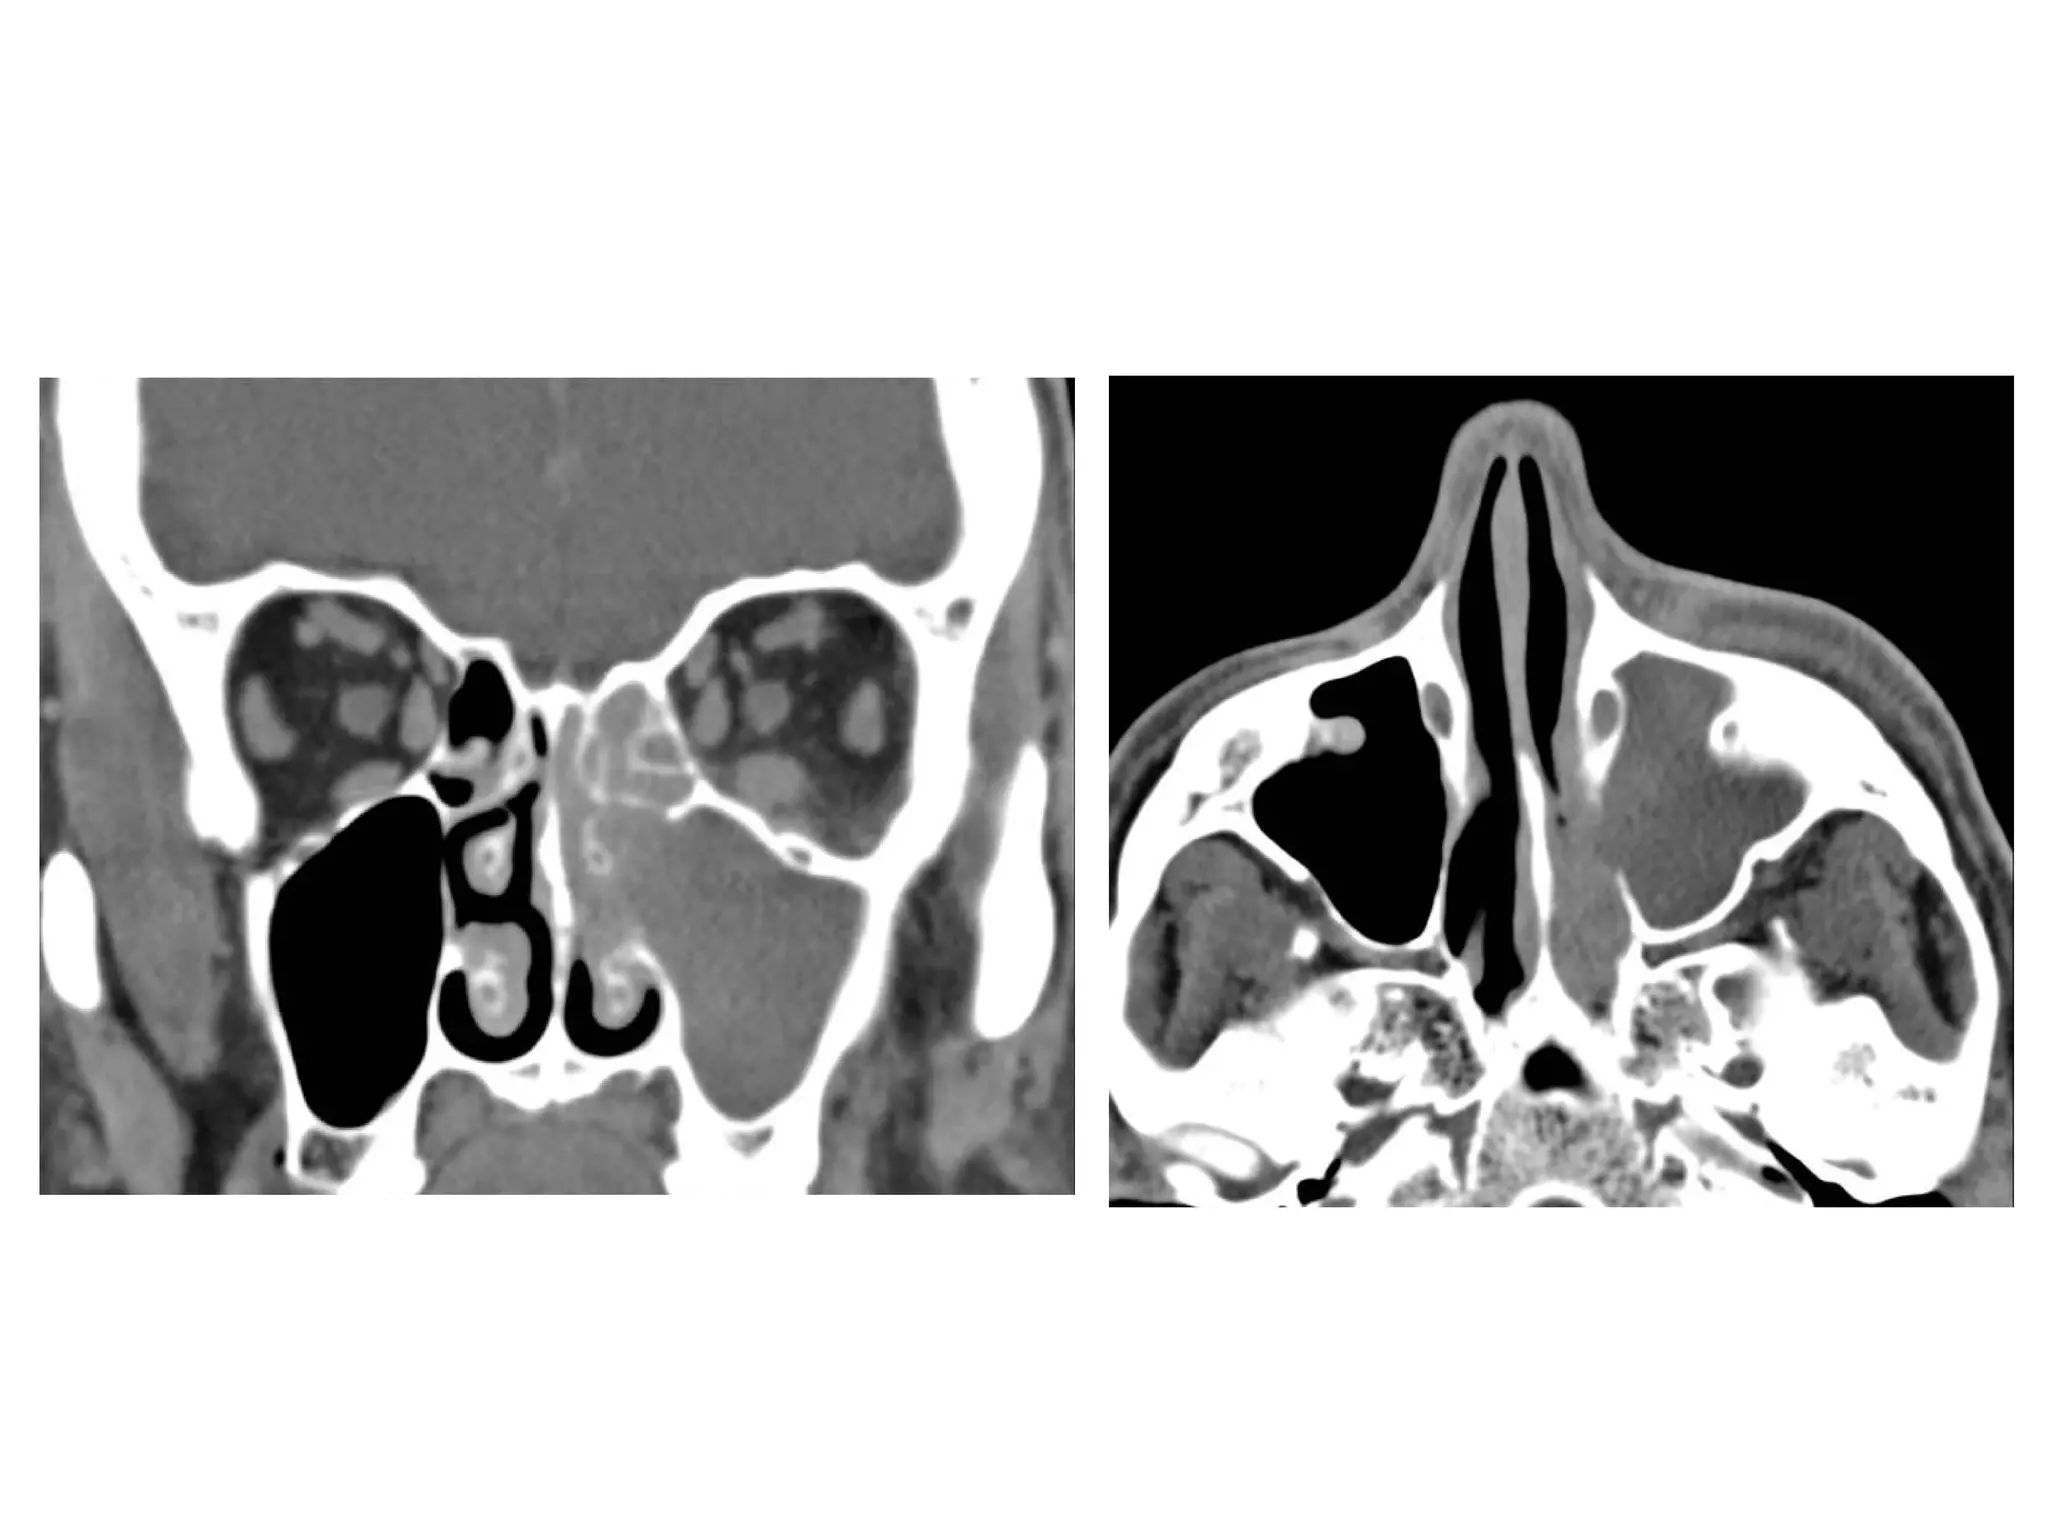

f) Mucocele :

1-Incidence

2-Location

3-Radiographic Features

1-Incidence :

-True cystic lesion lined by sinus mucosa

-Mucoceles occur as a result of complete

obstruction of sinus ostium (inflammation ,

trauma & tumor)

-The bony walls of the sinus are remodeled

as the pressure of secretions increases

-In pediatric patients , consider cystic

3-Radiographic Features :

-Rounded soft tissue density

-Typically isodense on CT

-MR signal intensity :

Low T1 , high T2 : serous content

High T1 , high T2 : high protein content

Dark T1 and T2 : viscous content

-Distortion and expansion of bony sinus walls

-Nonenhancement unless infected (mucopyocele) ,

rim enhancement

-Complication : breakthrough into orbit or anterior

cranial fossa

Mucocele of the frontal sinus

Mucocele of the sphenoid and ethmoid sinuses